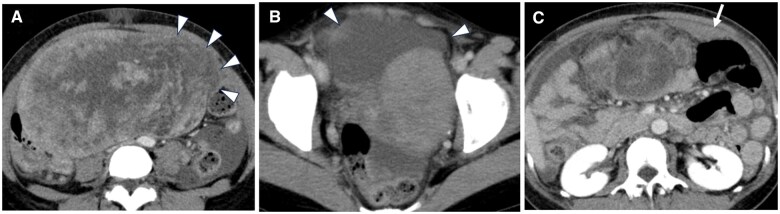

This case report describes a 47-year-old premenopausal woman who presented with abdominal discomfort and had been previously monitored for a suspected uterine leiomyoma. MRI revealed a 15 cm mass within the uterine body and slight intratumoural haemorrhage. One month later, the patient presented with acute abdominal pain and was admitted to the hospital. Contrast-enhanced CT and MRI scans showed significant tumour enlargement to 20 cm, with disruption along the left margin, haemorrhagic ascites, and potential dissemination to the omentum. Total hysterectomy, bilateral salpingo-oophorectomy, and retroperitoneal lymph node dissection revealed uterine leiomyosarcoma with extensive necrosis and rupture. Pathological examination classified the tumour as stage IIB under the International Federation of Gynecology and Obstetrics system, with confirmed omental metastasis. Despite adjuvant chemotherapy, the patient experienced pelvic recurrence 10 months later and died 15 months postoperatively. This case emphasizes the importance of prompt gynaecological intervention for uterine masses exceeding 10 cm, as the risk of rupture increases, particularly when malignancy cannot be excluded based on imaging. Rupture in such cases is associated with a higher risk of recurrence and poor prognosis, making early surgical resection a reasonable consideration. Radiologists should actively communicate these risks to gynaecologists to facilitate timely surgical decision-making and improve patient outcomes.